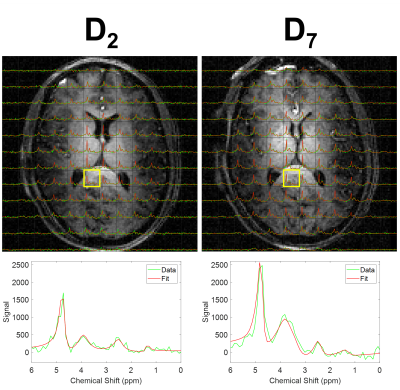

Figure 2 displays CSI data from one slice after averaging over six measurements made following D2-glucose or D7-glucose ingestion. Spectra and fits are shown overlaid on the corresponding MPRAGE images. Interpolated maps of metabolite signal amplitude derived from the fits in Figure 2 are shown overlaid on the MPRAGE image in Figure 3.

Figure 2. CSI data from one slice from the 3D data set (FOV = 180x180x120 mm3, 15mm resolution, apodised using 5 Hz exponential filter) measured from the same participant after ingestion of D2-glucose (left) and D7-glucose (right) in separate experimental sessions. Spectra were produced by averaging over six CSI scans acquired during each session and are overlaid on the corresponding slice of the MPRAGE image acquired in that session. Experimental data (green) and fits (red) are shown for each voxel. The spectra from the highlighted voxels are shown in detail in the lower plots.